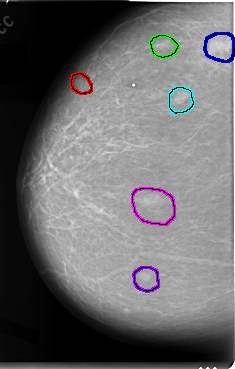

FILE: C_0025_1.RIGHT_MLO.OVERLAY

TOTAL_ABNORMALITIES 6

ABNORMALITY 1

LESION_TYPE MASS SHAPE ROUND MARGINS CIRCUMSCRIBED

ASSESSMENT 2

SUBTLETY 5

PATHOLOGY BENIGN

ABNORMALITY 2

ABNORMALITY 3

ABNORMALITY 4

ABNORMALITY 5

ABNORMALITY 6